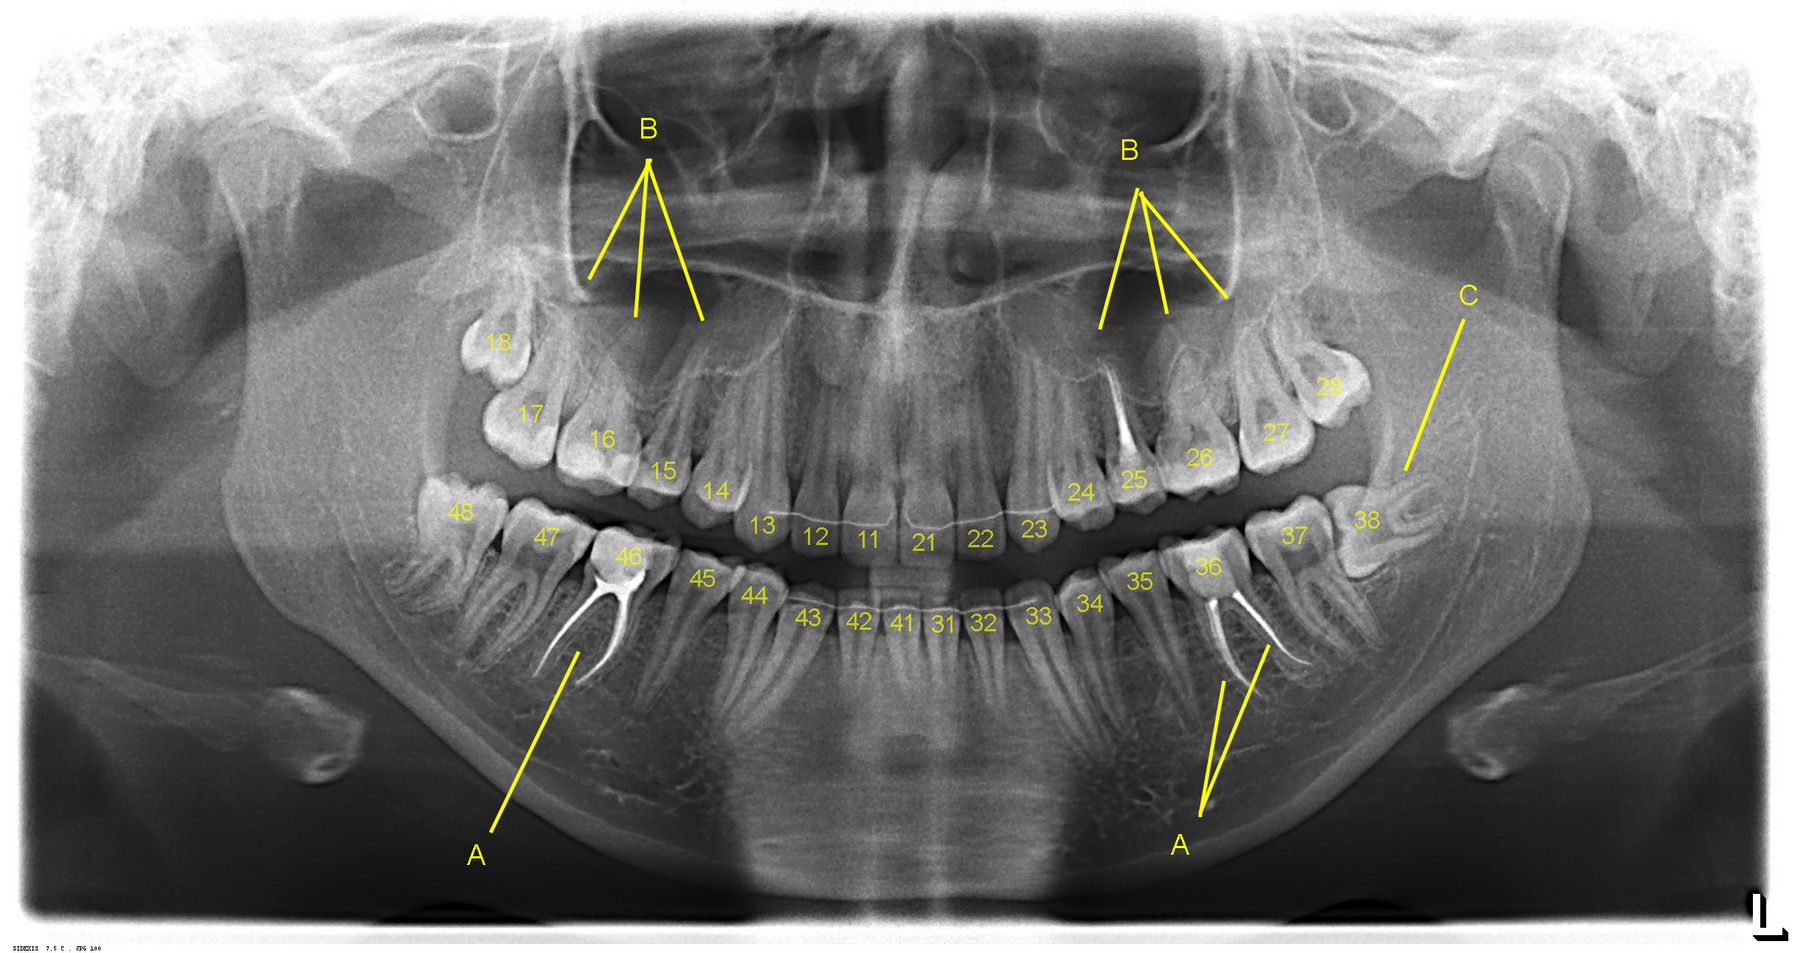

В современной стоматологии используется цифровое обозначение зубов. Вот так, как на расшифровке ортопантомограммы:

Другими словами, каждому сегменту зубного ряда присвоен десятичный разряд: правый верхний — «1..», левый верхний — «2..», нижний левый — «3..», нижний правый — «4..».

А по этой схеме и получается, что наш нижний левый первый моляр будет тридцать шестым зубом. то есть 36 зуб («3..» — нижний левый сегмент, а «..6» — порядковый номер зуба от центра).